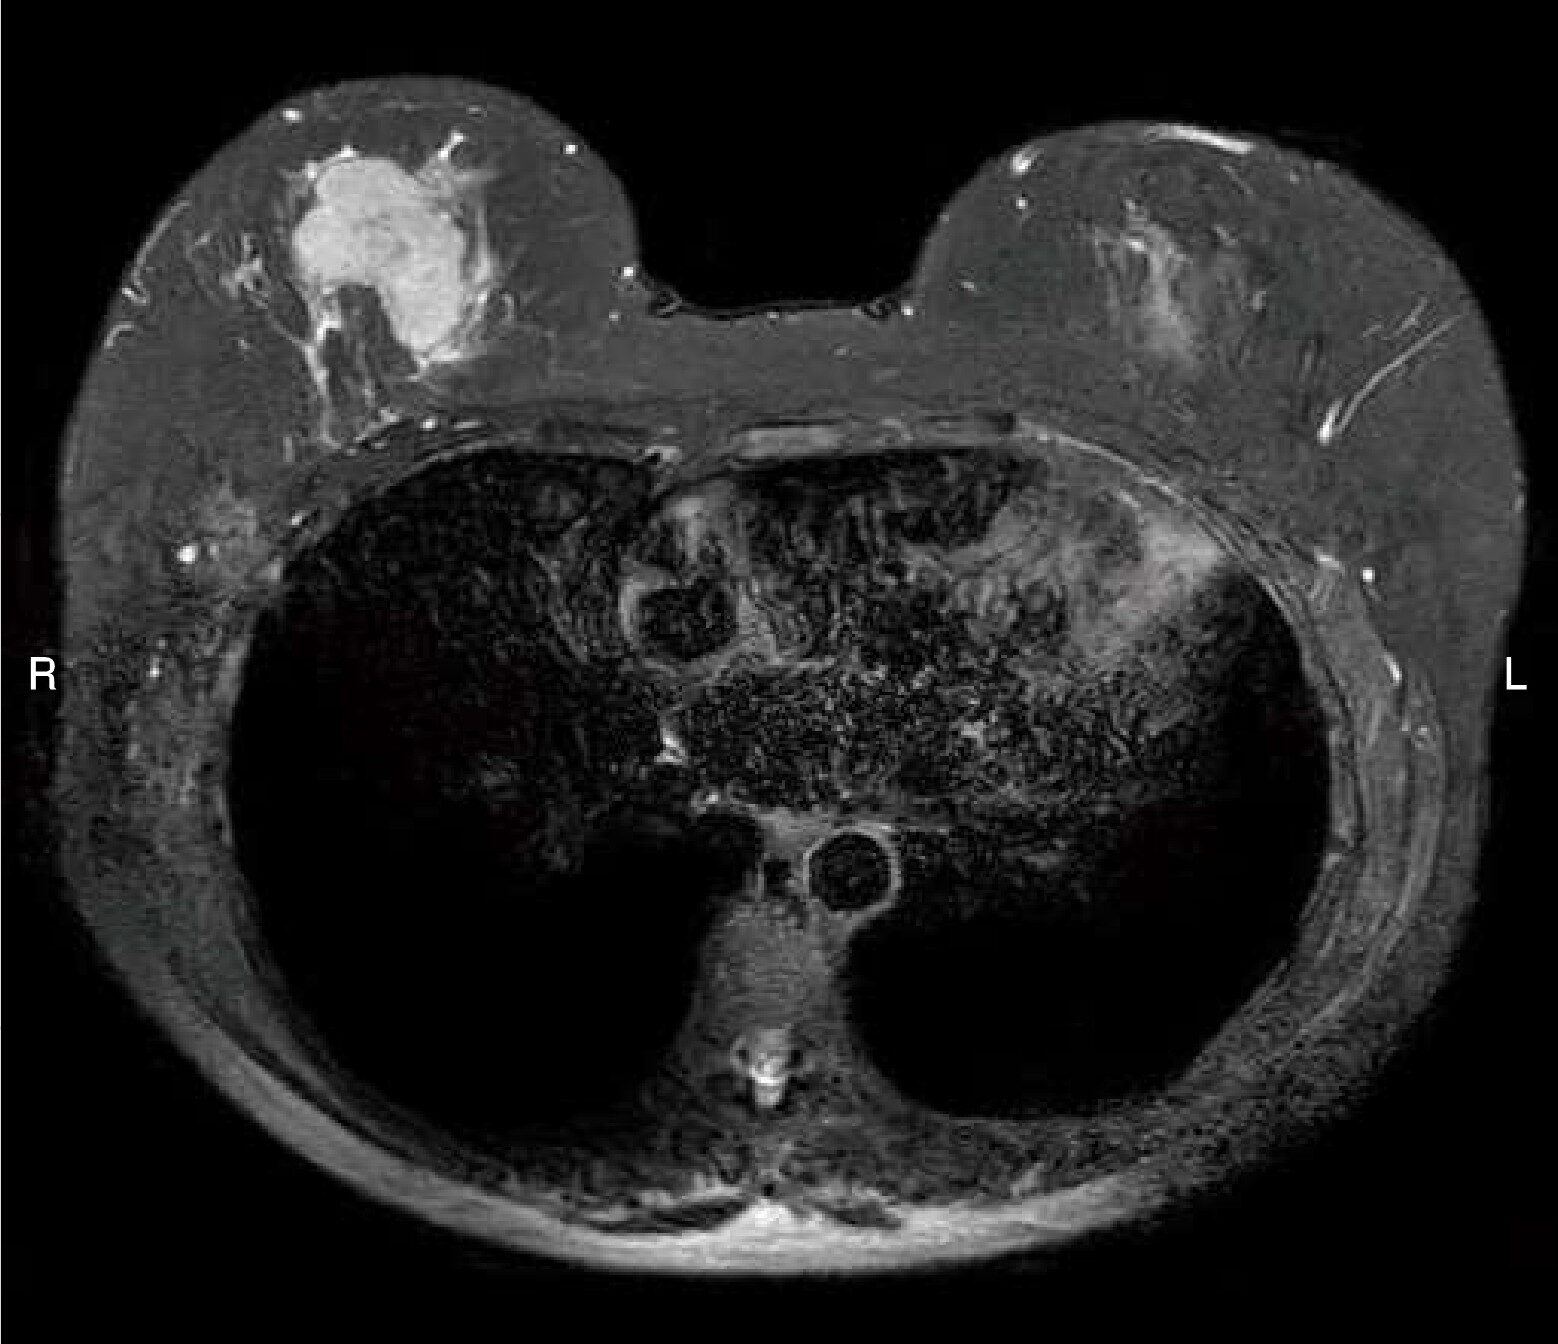

乳房のMR像(別冊No.1)を別に示す。この画像で正しいのはどれか。

- 1T1強調像である。

- 2位相方向は前後方向である。

- 3脂肪抑制法が併用されている。

- 4右乳房腫瘤は骨格筋と比較し低信号である。

- 5大動脈の内腔は高信号として描出されている。